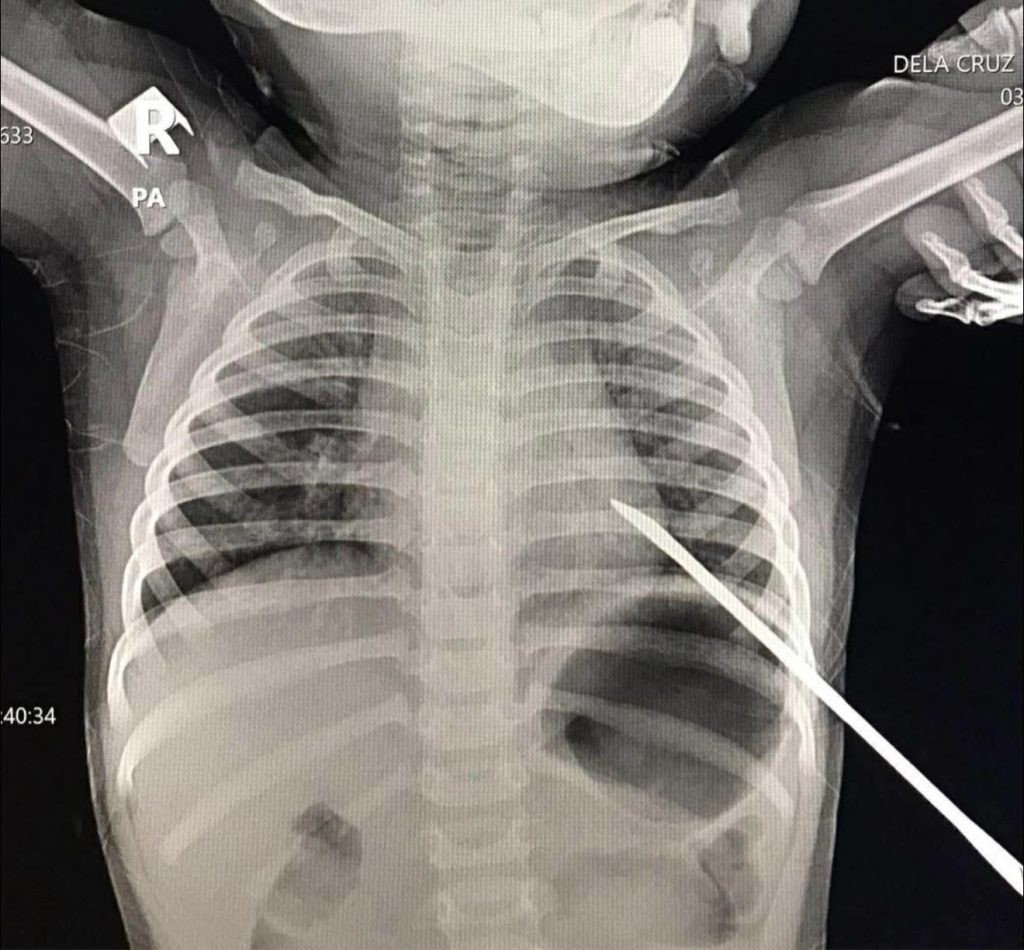

BONGAO, Tawi-Tawi — A one-year-old child who sustained a life-threatening impaled chest wound caused by a sharp pedicure tool locally known as a “nail pusher” has survived following a successful emergency operation at the province’s lone surgical hospital, according to a report aired by Suwara Tawi-Tawi, a local radio station.

The child was rushed to the Dr. Haji Sangkula J. Laja District Hospital (DHSMH) after accidentally falling while holding the steel object, which pierced the chest. Despite the severity of the injury, the hospital’s surgical team managed to safely remove the object and perform the necessary procedures.

“The removal of the object was successful, and appropriate surgical procedures were carried out,” Laja said in an interview cited by the radio report. “The patient is now stable.”